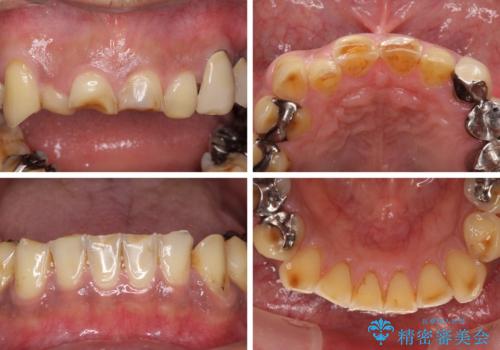

- すり減った前歯や奥歯の銀歯を気にして来院された患者様です。

骨格的な反対咬合により上顎前歯の先端が顕著にすり減っている状態でした。

奥歯の欠損が散見されており、銀歯の装着されている歯も多いため、ワイヤー矯正にて歯列を調整し、その後オールセラミッククラウンにて補綴治療を行うこととしました。